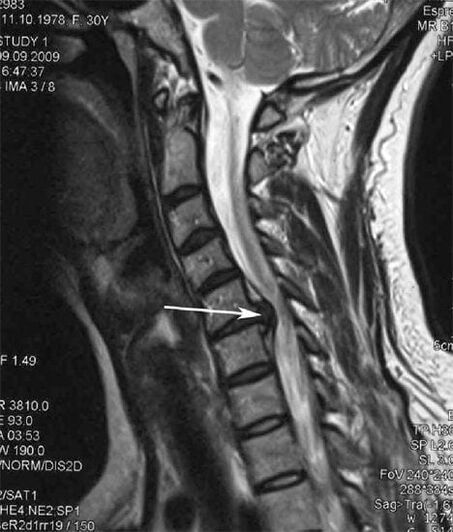

Im Anfangsstadium wird Osteochondrose mittels MRT erkannt. Später kann die Pathologie mithilfe der Radiographie diagnostiziert werden. Auf Röntgenaufnahmen der Halswirbelsäule machen sich eine Verringerung des Wirbelabstands, pathologische Veränderungen der Facettengelenke und Osteophytose bemerkbar.

Viele Menschen klagen darüber, dass sie ihren Hals nicht drehen können, da starke Schmerzen auftreten, wenn sie plötzlich etwas Schweres heben. Dieses Phänomen deutet auf die Entstehung eines Bandscheibenvorfalls hin. Die Ursache für Schmerzen im Rücken, Nacken und in den oberen Gliedmaßen ist das Einklemmen einer der aus dem Rückenmark austretenden Nervenwurzeln.

| Zervikale Osteochondrose | Das Auftreten pathologischer Veränderungen in einem oder mehreren Bewegungssegmenten der Wirbelsäule. Beeinträchtigte Beweglichkeit der Wirbelsäule, Entwicklung myofaszialer Schmerzsyndrome und Einklemmen der Wirbelsäulenwurzeln | Schmerzen, Parästhesien und motorische Störungen im Halsbereich, die sich auf den Hinterkopf und die oberen Gliedmaßen ausbreiten. Erkennung charakteristischer Veränderungen der Wirbelsäule im MRT und im Röntgenbild (Osteophyten, verringerter Wirbelabstand, Anzeichen einer Schädigung der Zwischenwirbelgelenke) |